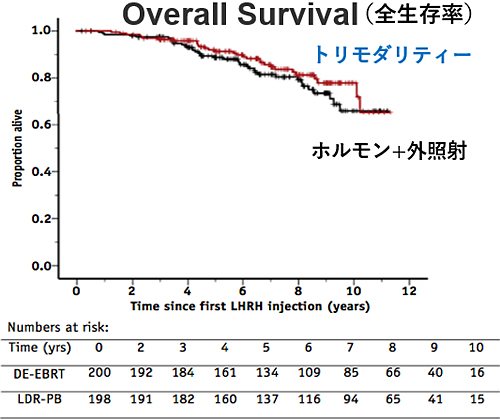

トリモダリティ療法の効果は?

高リスクがんに対する治療効果

現状では高リスクの前立腺がんに対して、最もPSA再発(生化学的再発)が少ないと考えられる治療法です。